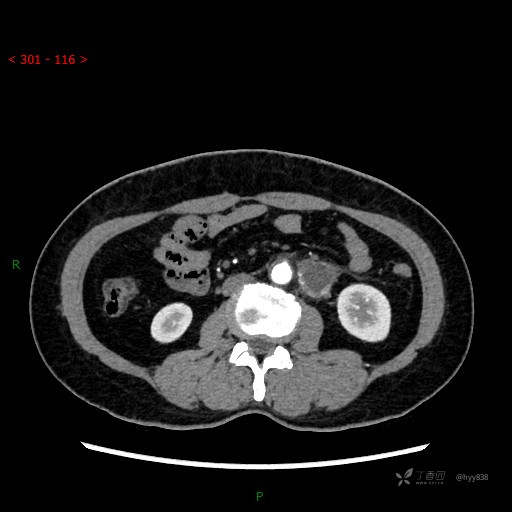

增强动脉期

静脉期